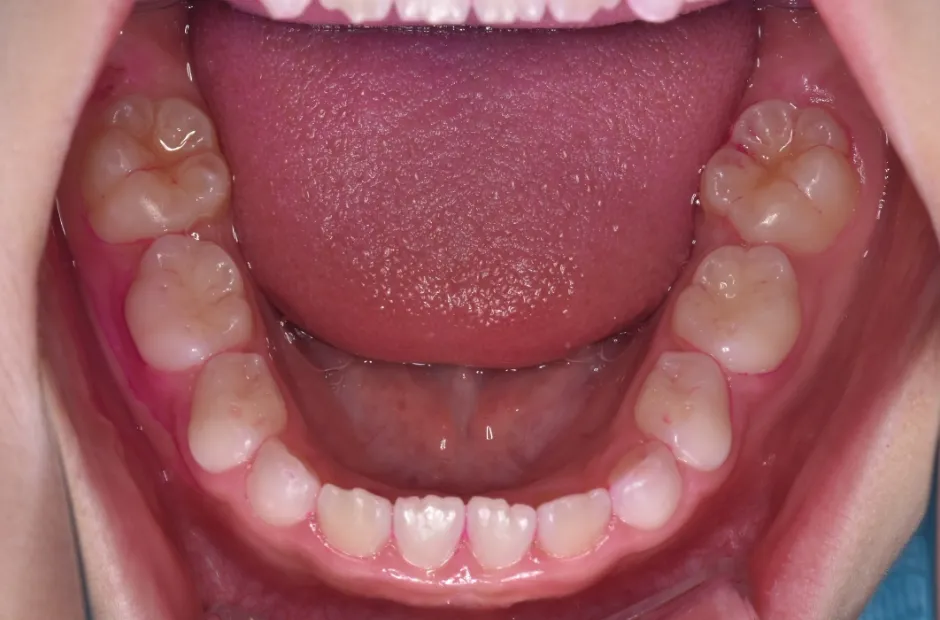

舌側弧線装置(タングクリブ付)

開咬、すきっ歯

| 診断名・主訴 | 開咬、すきっ歯 |

|---|---|

| 年齢・性別 | 7歳・男性 |

| 治療期間・回数 | 3年 |

| 治療に用いた主な装置 | 舌側弧線装置(タングクリブ付) |

| 抜歯部位 | なし |

| 治療費 | 30万円(税抜) |

| リスク・副作用 | 装置による違和感・疼痛・歯肉退縮・歯根吸収・虫歯のリスクなど |

治療前

治療後